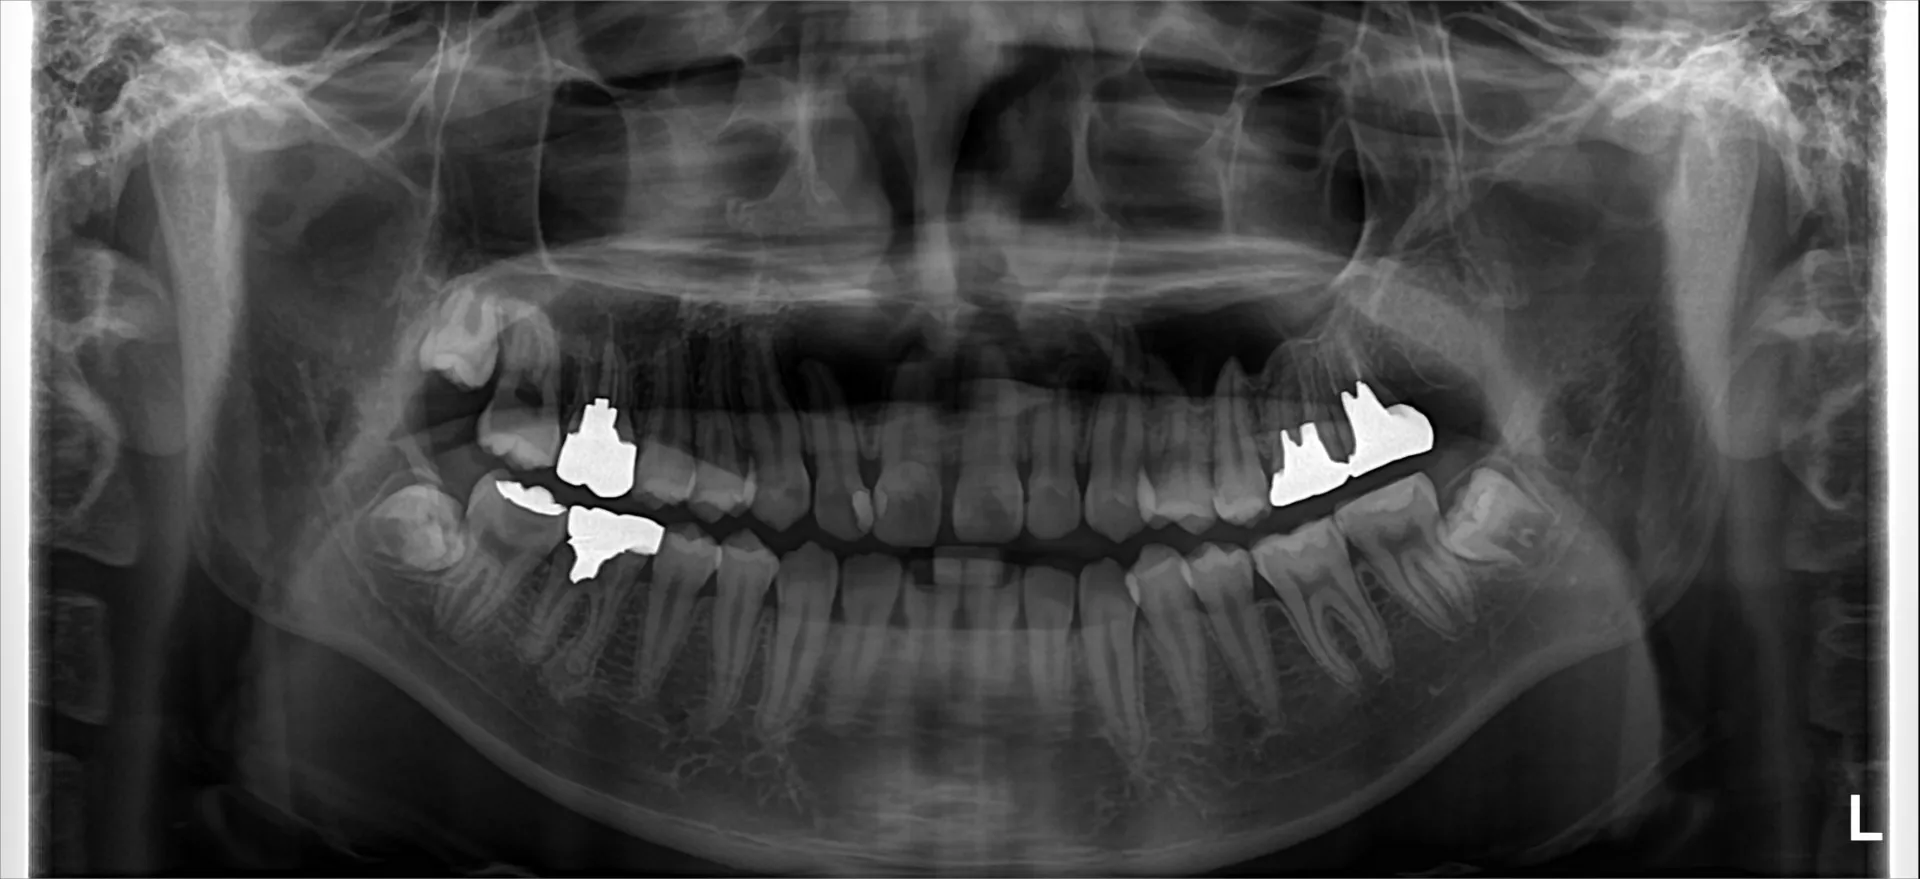

巨大な歯根膿瘍の根管治療1.5年経過症例 2025/06/24 こんにちは!千葉県市川市の妙典駅前にある妙典歯科Nクリニックです。歯の根っこ先に膿ができることはご存じでしょうか?歯の根っこの先に膿ができる病気を歯根膿瘍、または袋状になった物を歯根嚢胞と言…